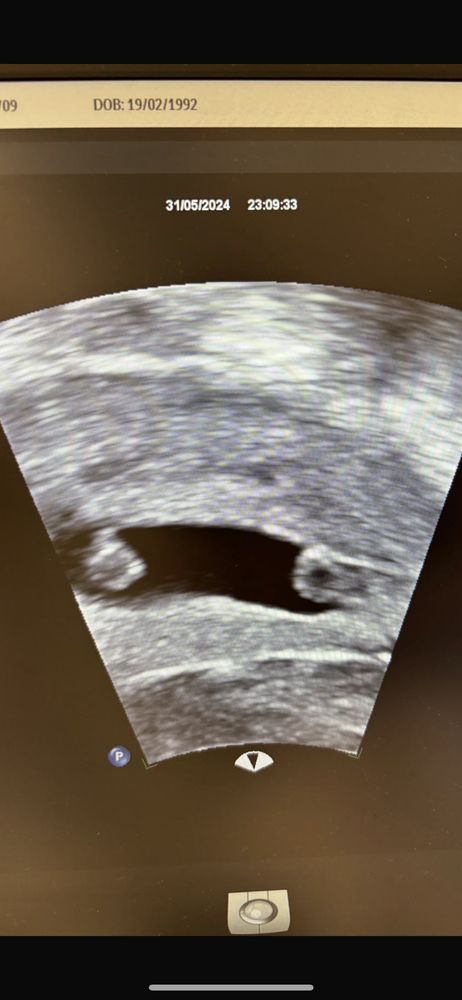

Юлия, Изображение Вот фото с узи. Дизиготные -исключены🤷🏻‍♀️ переносили 1 эмбрион (икси, значит оплодотворенный одним сперматозоидом). Крио протокол на згт. Мф, полностью исключающий естественное зачатие. Значит один эмбрион - поделился. Но они так далеко..

Юлия, теперь я поняла, что этот черный овал в центре (с 2мя эмбриончиками) -это не матка, это и есть плодное яйцо 🙈😅 а матка - серая толстая вокруг. Спасибо, что помогли разобраться 🙏🏻